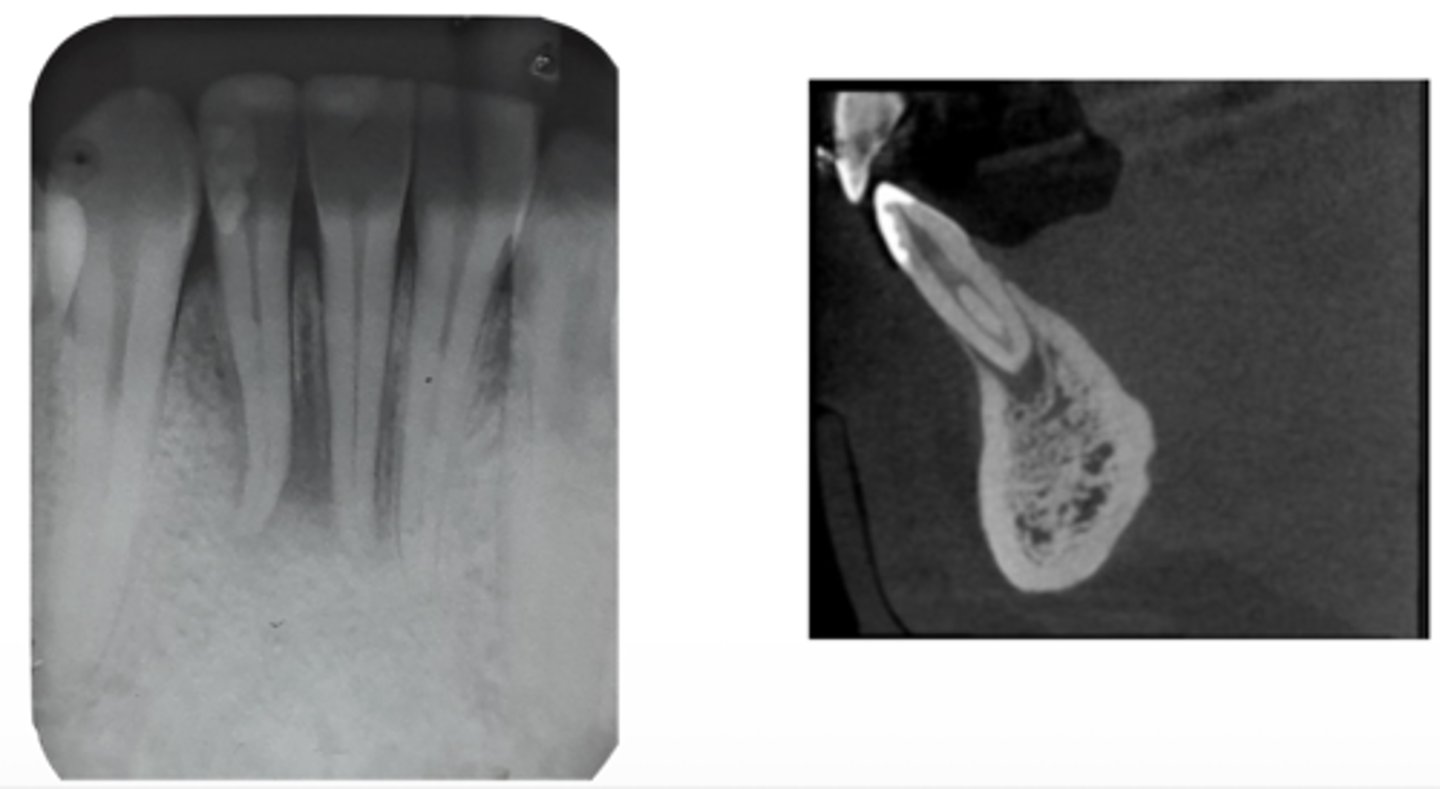

What are the radiographic findings on #19?

- Crown

- Post D Canal

- PARL Mesial and Distal Root

vertical root fracture

ID the problem:

- May not show on PA radiographs

Presents with signs of:

- J-shaped lesion/lateral radiolucency

- Isolated deep pocket

- Coronally located swelling or sinus tract